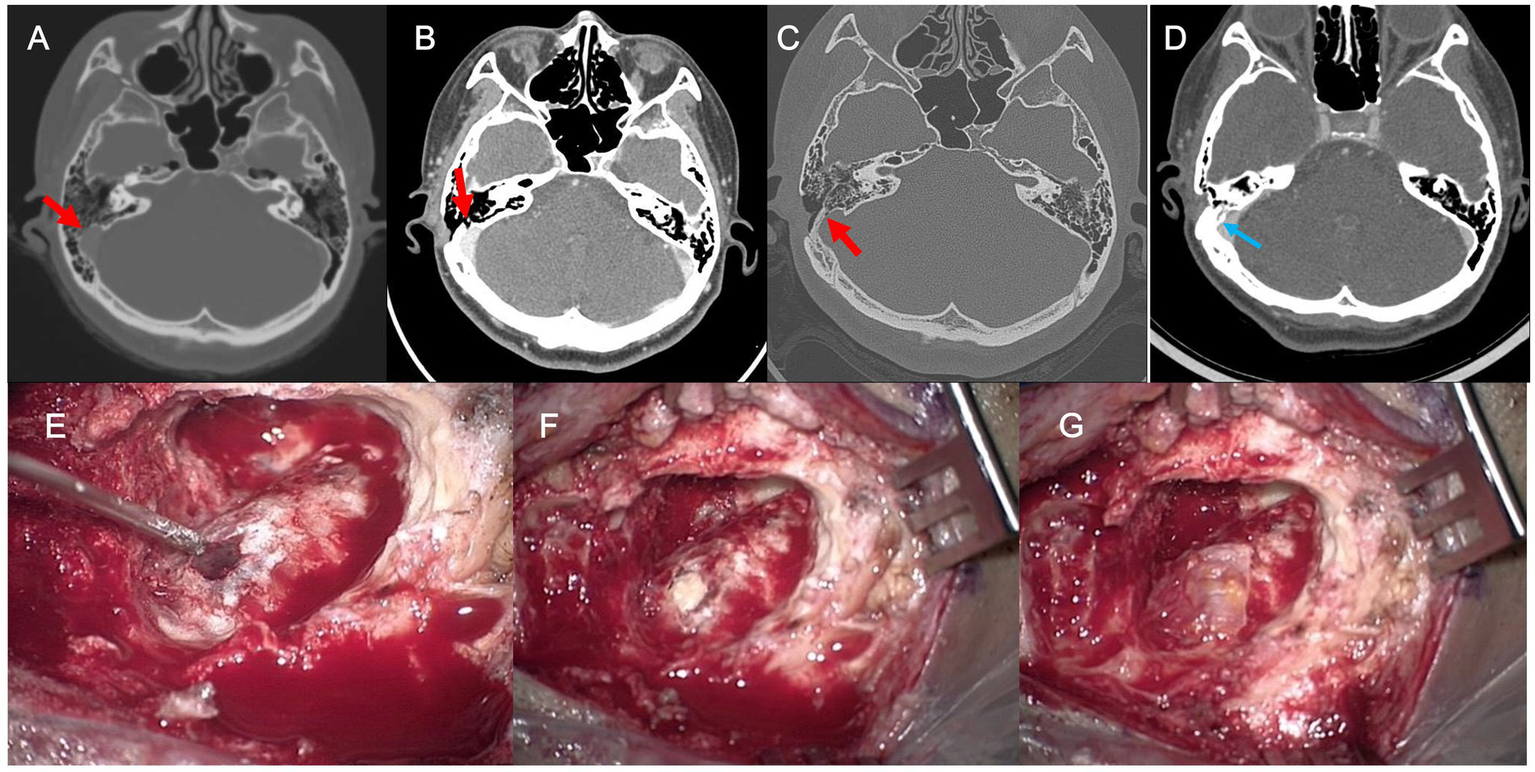

Figure 4

(A) Preoperative axial temporal bone computed tomography (TBCT) image of Subject 4 shows a huge diverticulum protruding through the mastoid air cells and cortical mastoid bone to the level of the subcutaneous soft tissue layer (arrow). (B) Postoperative axial TBCT image shows successful reduction of the diverticulum through transmastoid resurfacing with bone wax (arrow) and fibrin glue. (C) Follow-up TBCT axial image shows a huge diverticulum protruding through the mastoid air cells and cortical mastoid bone to the level of the subcutaneous soft tissue layer (arrow). (D) Again, the diverticulum is successfully reduced by transmastoid reshaping with harvested autologous cortical bone chips and bone cement (arrow). (E) The diverticulum was exposed to the mastoid cortex again. (F,G) Thus, revision reshaping of the sigmoid sinus diverticulum was performed with harvested autologous cortical bone chips and bone cement to reconstruct a secure sinus wall over the diverticulum.